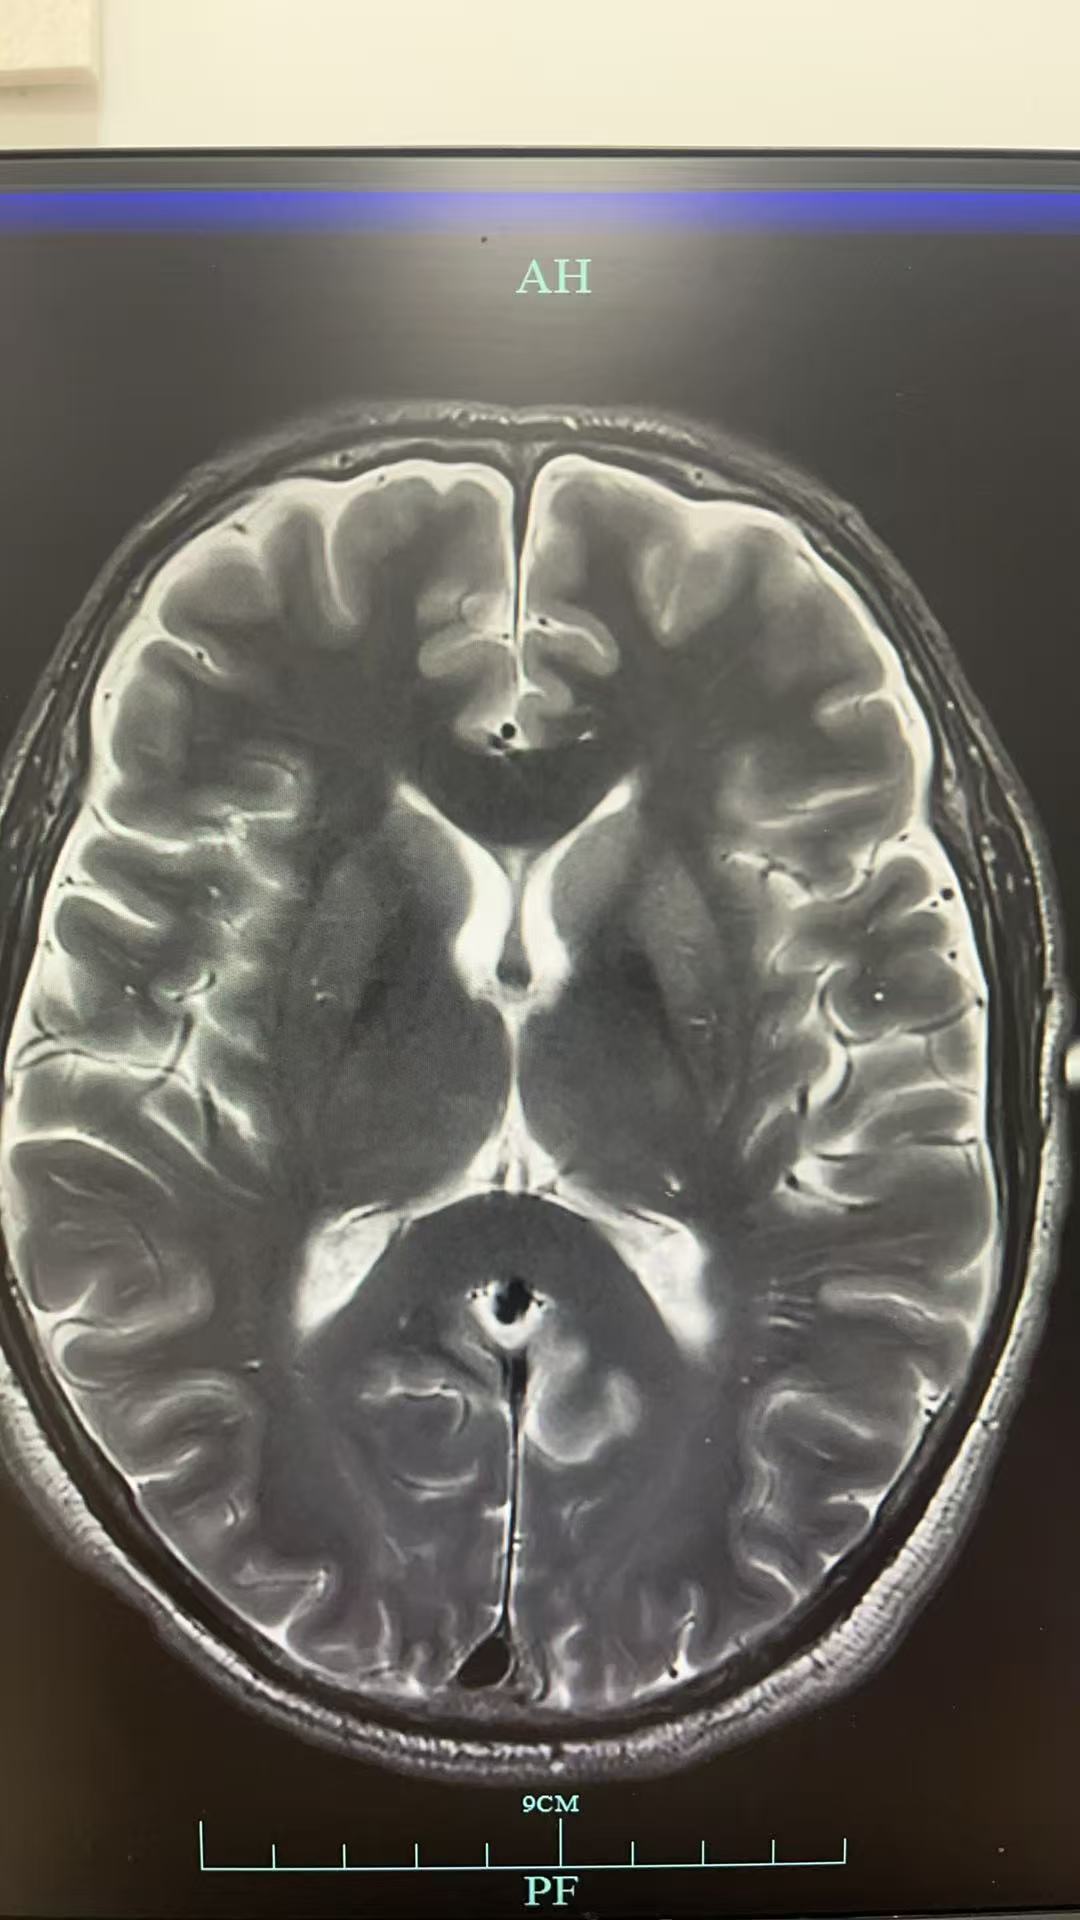

入ICU后因意识情况变差加重,给予气管插管有创机械通气治疗,后完善腰穿,压力正常范围,细胞数目无,并行脑脊液NGS检查,结果全阴;完善脑脊液自免脑抗体检查,结果仍旧为阴性。期间做头颅MRI检查提示:两侧大脑半球硬脑膜增厚强化,请结合临床。右侧额及两侧沈叶可疑部分柔脑膜强化,请结合临床。

神经内科梁主任会诊后认为:患者二月前出现头晕,症状加重,一月前出现精神症状当地头颅MRI示左侧尾状核和枕叶DWI高信号,本院复诊尚可见硬脑膜强化意见,建议床边脑电图,复查腰穿查脑脊液RTQUICE排除克雅氏病可能。查血LGI1抗体,继续甲强龙治疗。随后送的LGI1抗体结果阴性,而脑脊液的RT-QuIC结果为阳性,因此诊断为克雅病。

本案例的突破点在于病史+脑MRI检查结果,对比指南可以看到我们的MRI在尾状核那边也有明显强化的表现。